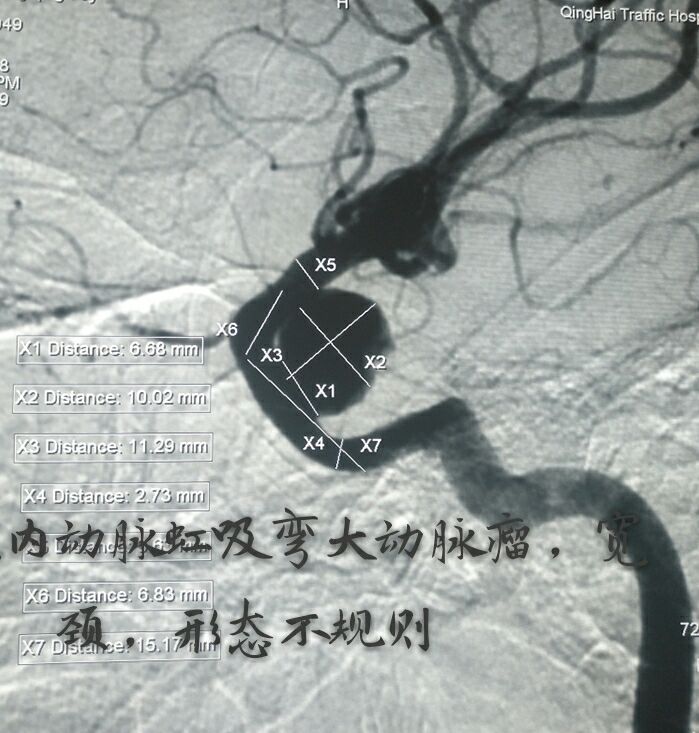

病例一:左侧颈内动脉虹吸弯大动脉瘤,宽颈,形态不规则

支架辅助+双微导管技术致密栓塞动脉瘤